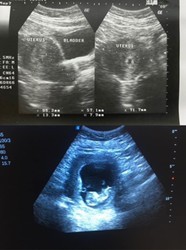

ภาพบน6week ภาพล่าง 12weekค่ะ US เห็นน้องตอน 9weekค่ะ แม่ใจเย็นๆนะคะ น้องยังเล็กมากอาจจะยังไม่เห็นค่ะ